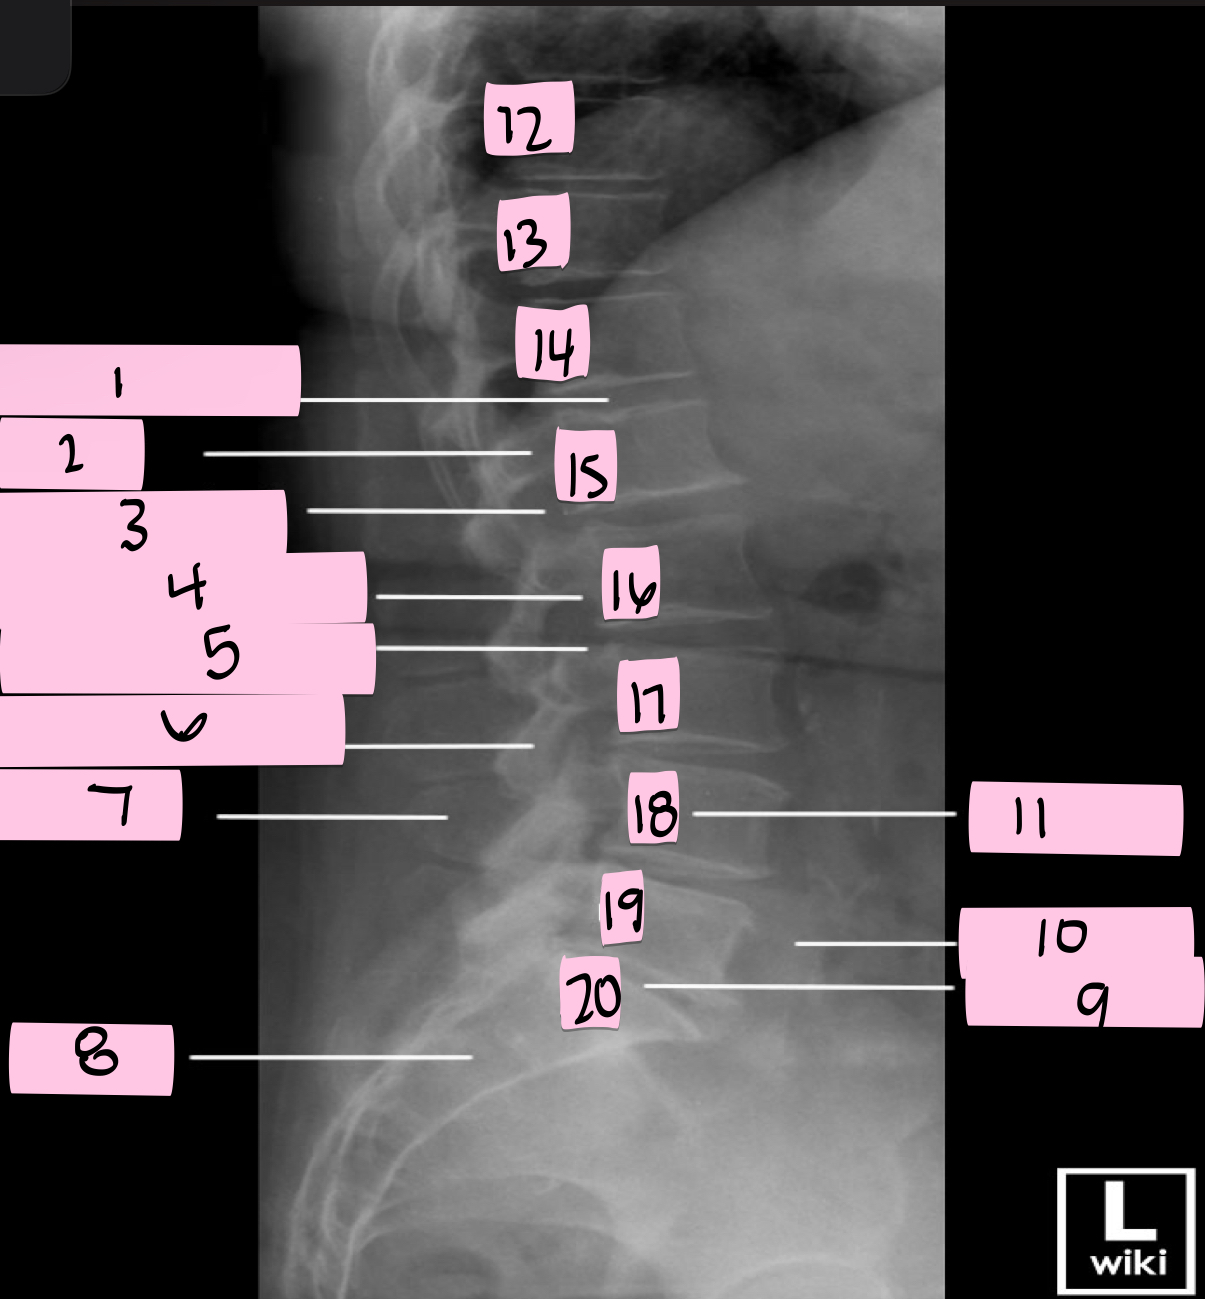

What is 1 pointing to?

Intervertebral disk

What is 2 pointing to?

Pedicle

What is 3 pointing to?

Intervertebral foramen

What is 4 pointing to?

Inferior vertebral notch

What is 5 pointing to?

Superior vertebral notch

What is 6 pointing to?

Inferior articular process

What is 7 pointing to?

Spinous process

What is 8 pointing to?

Sacrum

What is 9 pointing to?

L5 S1 joint

What is 10 pointing to?

Iliac crest

What is 11 pointing to?

Vertebral body (L4)

What is 12 pointing to?

T10

What is 13 pointing to?

T11

What is 14 pointing to?

T12

What is 15 pointing to?

L1

What is 16 pointing to?

L2

What is 17 pointing to?

L3

What is 18 pointing to?

L4

What is 19 pointing to?

L5

What is 20 pointing to?

S1